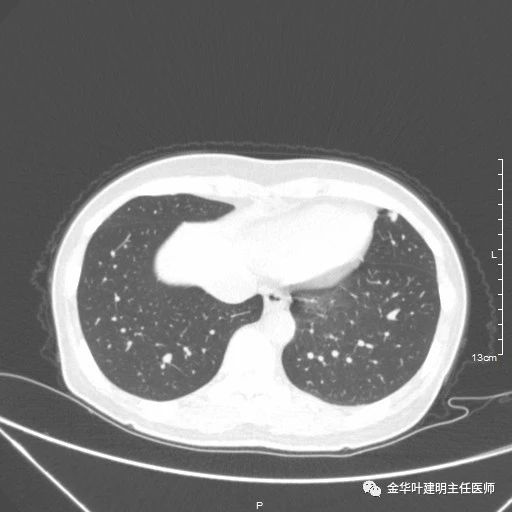

一、浸润性腺癌贴壁生长型:

影像特征:肺内纯磨玻璃结节,几乎不见实性成分;瘤肺边界清楚,紫色箭头示局部有细毛刺征;绿色箭头示有血管进入病灶;总体密度较低,轮廓清楚。要注意的是:贴壁生长型肺浸润性腺癌可以在2-3厘米或以上,也可小到亚厘米程度,密度高低可以有所区别,有时与原位腺癌、微浸润性腺癌、不典型增生等在影像学上有交叉,不能完全仅凭影像学区别。但总体上,恶性程度低,预后好。